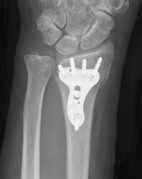

【骨折型に応じた各種プレート固定】

写真1

写真1:比較的シンプルな骨折に対する短いプレート固定